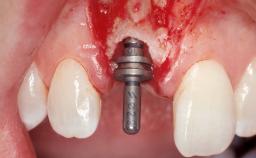

Immediate Placement of an Implant in a Maxillary Left Central Incisor Site

A 33-year-old female patient presented with an upper left central incisor that required extraction after a failed endodontic therapy. The tooth had been traumatized when the patient was a teenager and had undergone several endodontic treatments, including two apicectomy procedures. The patient was in good health and did not smoke. Clinical examination showed that the patient had a high lip line. In full smile, the gingival margins of the upper teeth were visible to the first molars. The gingival margins of central incisors 11 and 21 were only just showing. Examination of tooth 21 confirmed that the tooth was mobile and had hypererupted by 1 mm.

Placement Protocol Immediate implant placement

Tooth Site Maxillary incisor or canine

Socket Morphology Single-root socket

Socket Integrity Damage to one or more bone walls

Bone Volume Damage to one or more socket walls